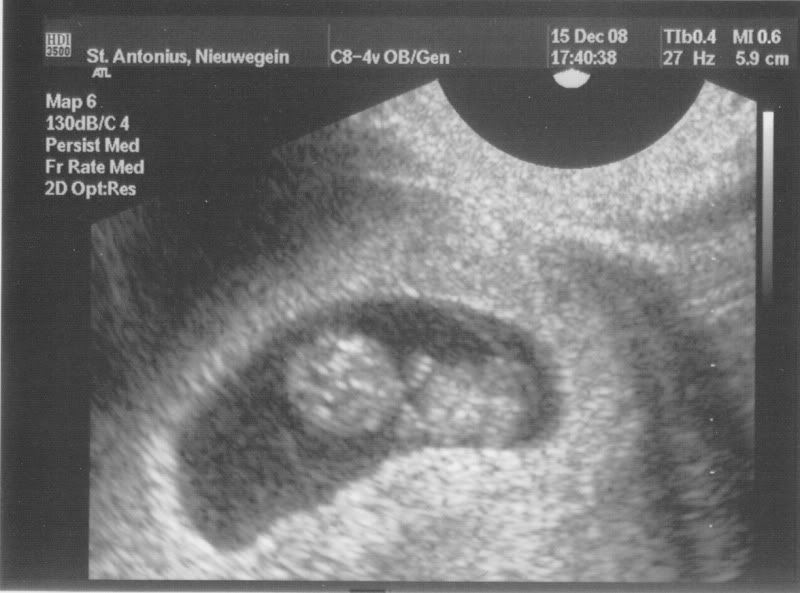

Nou we zijn vandaag voor de 1e echo geweest en het was echt super!!!

De kleine loopt goed op schema en we zijn rond 17 juli 2009 uitgerekend....

Ook was hij/zij erg bewegelijk en kon je de handjes goed zien, verder hebben ze geen afwijkingen gezien..

We hebben het hartje niet gehoord, maar wel zien kloppen! Ja was helemaal super!!